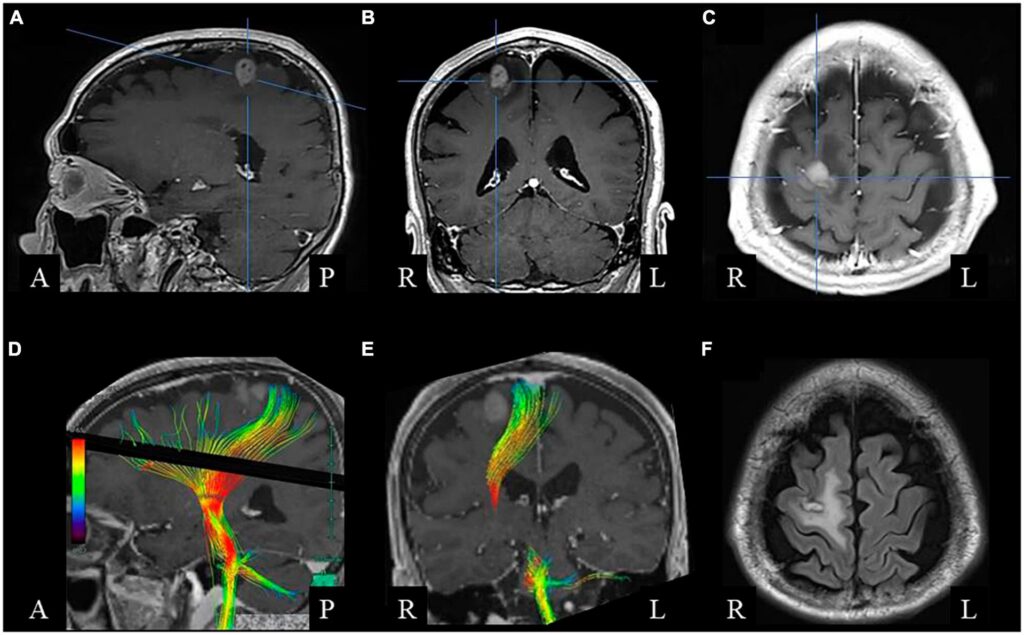

Para que la coordinación bimanual se lleve a cabo de manera efectiva, el sistema nervioso central debe codificar los requisitos espaciales y temporales del movimiento antes de que este ocurra. Además, la retroalimentación sensorial es crucial para actualizar estas codificaciones y permitir correcciones sobre la marcha. Pero, ¿qué mecanismos neuronales sustentan esta codificación y coordinación de las extremidades superiores? La investigación ha revelado que una amplia red de regiones cerebrales está implicada en la coordinación de ambas manos. Esta red incluye, entre otras, la corteza motora primaria (M1), la corteza premotora (PMC), el área motora suplementaria (SMA), el área motora cingulada (CMA), los ganglios basales y el cerebelo.

Al principio de la investigación sobre la coordinación bimanual, se propuso que la SMA controlaba exclusivamente la integración de las dos manos. Esta idea dominó la visión sobre los mecanismos neuronales de la coordinación motora bimanual durante mucho tiempo. Sin embargo, estudios más recientes han proporcionado evidencia anatómica y neurofisiológica de la existencia de una red neuronal más distribuida involucrada en el control del comportamiento motor bimanual coordinado. Por ejemplo, se ha demostrado que las redes neuronales dentro de M1 se activan de manera diferente durante tareas bimanuales y unimanuales. También se ha encontrado actividad relacionada con movimientos bimanuales en el área motora cingulada (CMA), la corteza premotora (PMC) y la corteza parietal posterior (PPC) durante la realización de tareas de coordinación bimanual.

Otro hallazgo que desafió el papel especial de la SMA provino de estudios de inactivación reversible de la SMA en primates. Estos estudios no resultaron en una pérdida de la capacidad de coordinar ambas manos en una tarea de agarre de cajones, sino que demostraron déficits en el inicio de secuencias de movimiento no marcadas externamente. Además, resultados de estudios recientes de neuroimagen también cuestionan la función especial propuesta para la SMA en movimientos bimanuales. Estos estudios han identificado una red consistente que incluye varias regiones corticales y subcorticales involucradas en la coordinación bimanual (cortezas motoras y sensoriales primarias y secundarias: M1/S1, PMC, SMA, CMA, el cerebelo (CB), y dependiendo de la tarea, la corteza parietal posterior (PPC)).